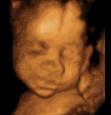

三维超声是在二维的基础上,增加表面成像功能,呈现的是立体图像。

四维彩超能看到宝宝在肚子里的动作和表情,想把彩超的图像作为宝宝人生的第一张照片来收藏,首选四维彩超~

麻麻,我有点累了,换个姿势~

在妈妈肚子里最舒服了,我睡的很香哦!